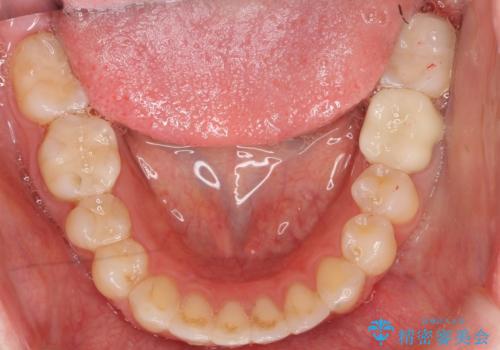

手術後、きちんとマージンラインが歯肉の上に来た状態で、セラミックインレー修復を行いました。

- 38万円(左下7:歯周外科処置5万円、セラミックインレー7万円 左下6:精密根管治療(再治療・専門医による)13万円、ファイバーコア2万円、ジルコニアクラウン10万円、仮歯1万円)費用は治療当時の料金となります

レーザーや電気メスで分厚い歯肉を焼いても一時的で、やがてまた元のように歯ぐきが上まで増殖しますので、今回は骨の厚みも調整し、7番の遠心を出来るだけ下げました。